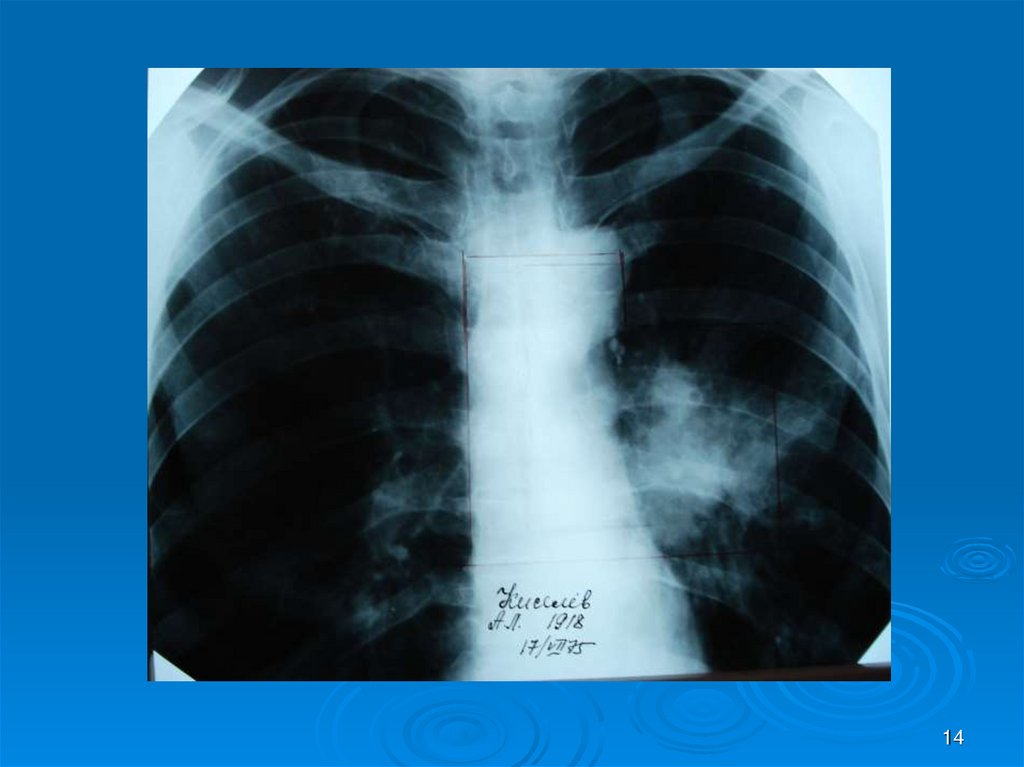

14.

14